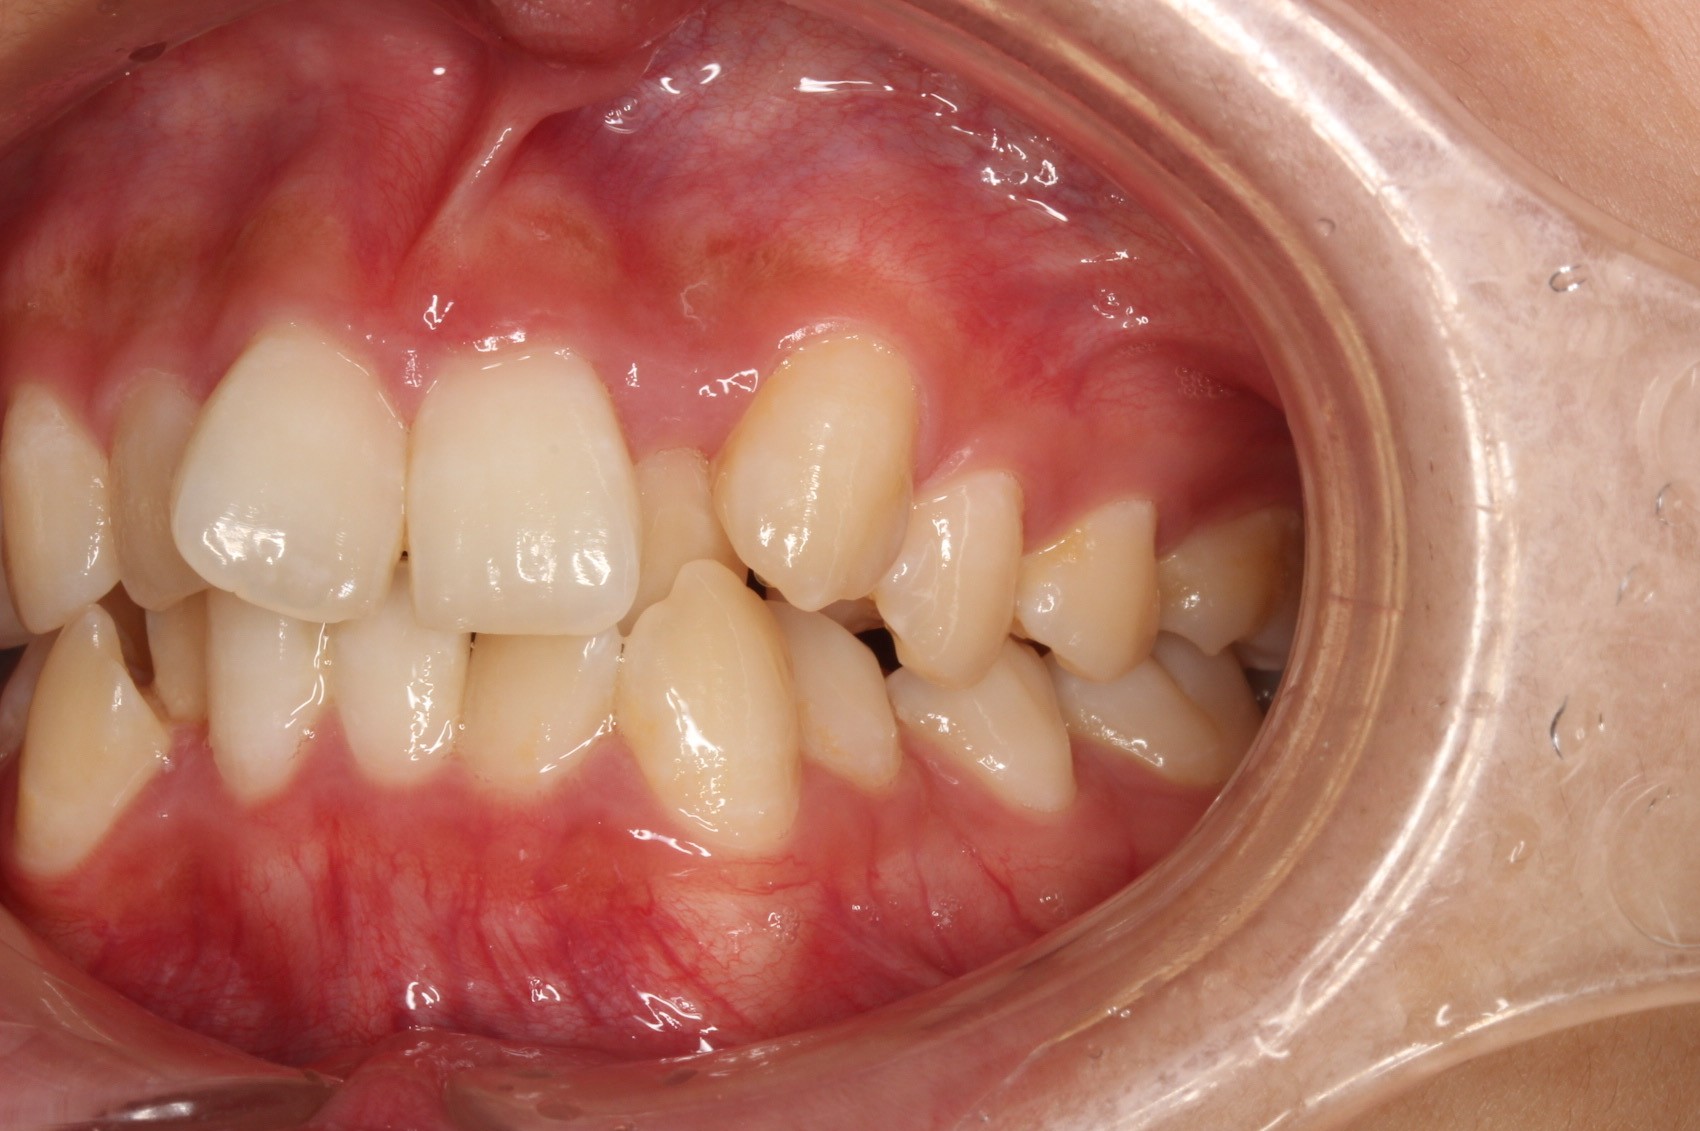

矯正術前:右側

矯正術後:右側